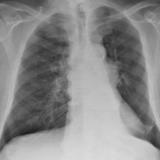

Lung Cancer

Nodules & Masses

Album: Nodules & Masses

Date: 01/25/2006

Size: 37 items

Views: 59064